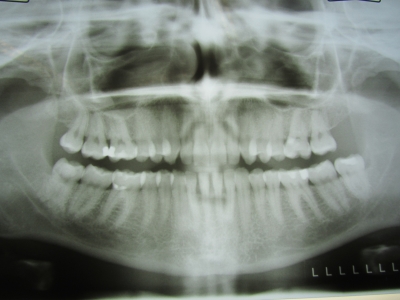

Sie sind hier: Startseite Nachrichten Gesundheit Studie: Zahnärztliche Röntgenaufnahmen erhöhen Risiko auf Hirntumor Bild: Liza Litsch / pixelio.de